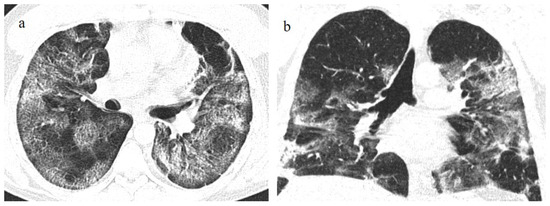

- Melhorn, J.; Achaiah, A.; Conway, F.M.; Thompson, E.M.; Skyllberg, E.W.; Durrant, J.; Hasan, N.A.; Madani, Y.; Naran, P.; Vijayakumar, B.; et al. Pneumomediastinum in COVID-19: A phenotype of severe COVID-19 pneumonitis? The results of the United Kingdom (POETIC) survey. Eur. Respir. J. 2022, 60, 2102522. [Google Scholar] [CrossRef]

- Khaire, N.; Deshmukh, S.; Agarwal, E.; Mahale, N.; Khaladkar, S.; Desai, S.; Kulkarni, A. “Pneumomediastinum: A marker of severity in COVID-19 disease”. Heliyon 2023, 9, e12981. [Google Scholar] [CrossRef] [PubMed]

- Tetaj, N.; Garotto, G.; Albarello, F.; Mastrobattista, A.; Maritti, M.; Stazi, G.V.; Marini, M.C.; Caravella, I.; Macchione, M.; De Angelis, G.; et al. Incidence of Pneumothorax and Pneumomediastinum in 497 COVID-19 Patients with Moderate–Severe ARDS over a Year of the Pandemic: An Observational Study in an Italian Third Level COVID-19 Hospital. J. Clin. Med. 2021, 10, 5608. [Google Scholar] [CrossRef] [PubMed]

- Coppola, M.G.; Lugarà, M.; Tamburrini, S.; Madonna, P.; Panico, C.; Noschese, G.; Pone, E. Pneumomediastinum and Pneumothorax as Relevant Complications of Sub-Intensive Care of Patients with COVID-19: Description of a Case Series. Medicina 2021, 57, 919. [Google Scholar] [CrossRef]

- Palumbo, D.; Campochiaro, C.; Belletti, A.; Marinosci, A.; Dagna, L.; Zangrillo, A.; De Cobelli, F. Pneumothorax/pneumomediastinum in non-intubated COVID-19 patients: Differences between first and second Italian pandemic wave. Eur. J. Intern. Med. 2021, 88, 144–146. [Google Scholar] [CrossRef]